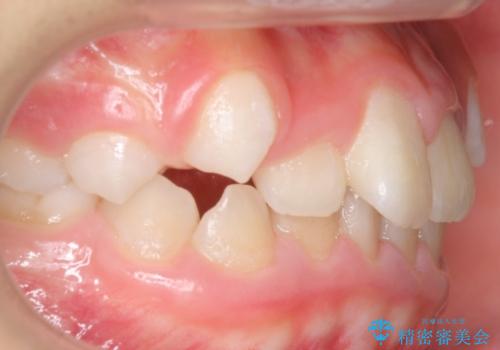

八重歯 歯を抜かずにインビザラインで

- 八重歯を主訴に来院。

抜かずに歯を少し削って入れる方法で並べました。

10代のうちに矯正をしておくと歯の移動は簡単で、歯ぐきも下がりにくいです。